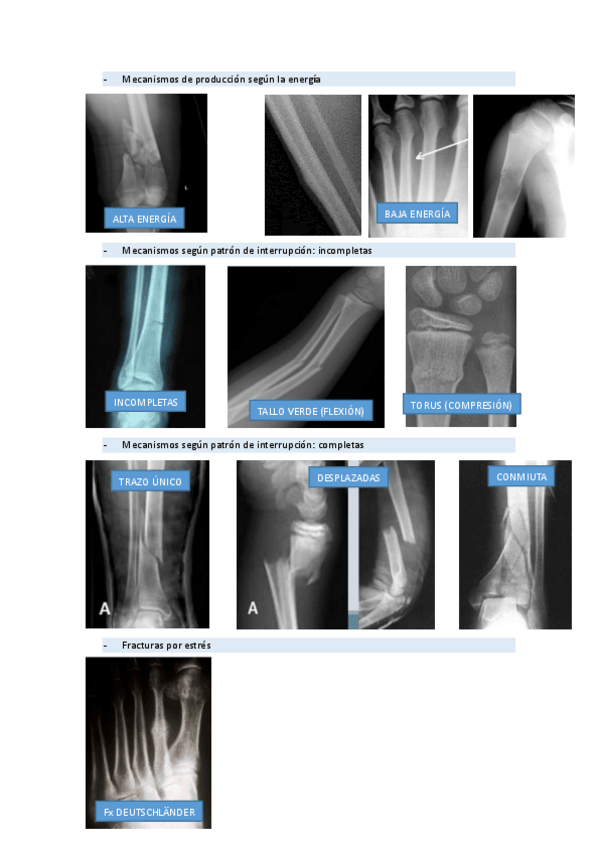

RADIOGRAFIAS PAT.QUIRURGICA

He publicado nuevos apuntes de 2º Patología Quirúrgica: RADIOGRAFIAS PAT.QUIRURGICA

rx-2.pdf

rx-1.pdf